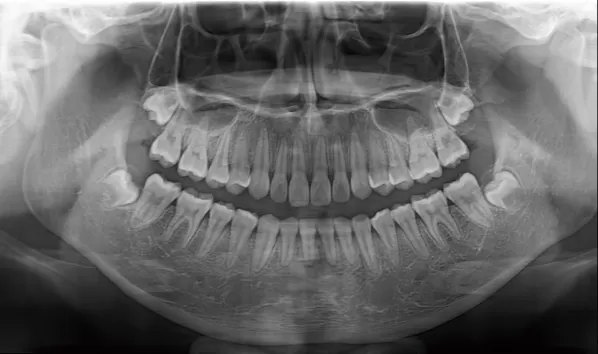

Rayons X avant le traitement

[Radiographie panoramique/Céphalogramme latéral]